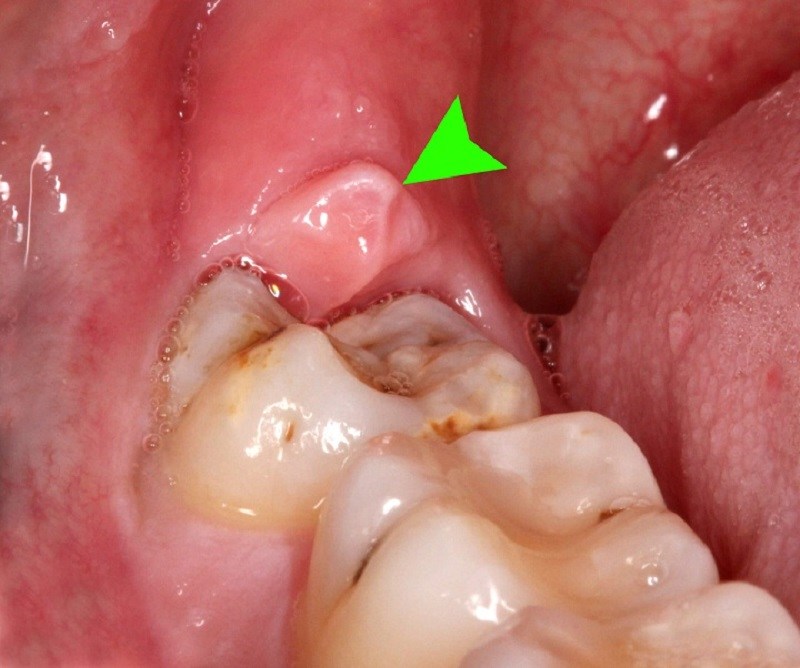

Hình ảnh lợi bị sưng khi mọc răng khôn

- Sưng lợi: ở độ tuổi trưởng thành, phần lợi đã chắc lại và xương hàm không còn phát triển nữa nên khi mọc răng khôn, lợi sẽ bị dãn ra và phồng lên.

- Đau nhức quanh vùng lợi: ngay khi răng khôn bắt đầu nhú lên, bạn sẽ cảm thấy đau nhức. Ban đầu sẽ chỉ là đau nhức quanh vùng lợi mọc răng, theo thời gian, nếu răng khôn không mọc thẳng mà mọc lệch, mọc sai vị trí sẽ gây đau răng hàm bên cạnh và các vùng còn lại của khoang miệng.